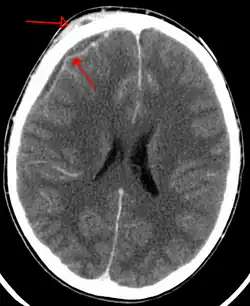

An abscess that has led to an intracranial subdural empyema as seen on CT

Subdural empyema is a form of empyema โ€“ a collection of pus, in the subdural space.

Bacterial or occasionally fungal infection of the skull bones or air sinuses can spread to the subdural space, producing a subdural empyema. The underlying arachnoid and subarachnoid spaces are usually unaffected, but a large subdural empyema may produce a mass effect. Further, a thrombophlebitis may develop in the bridging veins that cross the subdural space, resulting in venous occlusion and infarction of the brain. With treatment, including surgical drainage, resolution of the empyema occurs from the dural side, and, if it is complete, a thickened dura may be the only residual finding. Symptoms include those referable to the source of the infection. In addition, most patients are febrile, with headache and neck stiffness, and, if untreated, may develop focal neurologic signs, lethargy, and coma. The CSF profile is similar to that seen in brain abscesses, because both are parameningeal infectious processes. If diagnosis and treatment are prompt, complete recovery is usual.